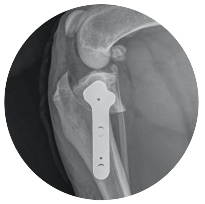

What is a TPLO?

OssAbility Guided TPLO is a surgical treatment your vet can tailor specifically to your pet. It is only performed by vets that are trained and confident in the procedure. TPLO is the gold-standard surgery for treating cruciate disease because it provides the best long term limb function.